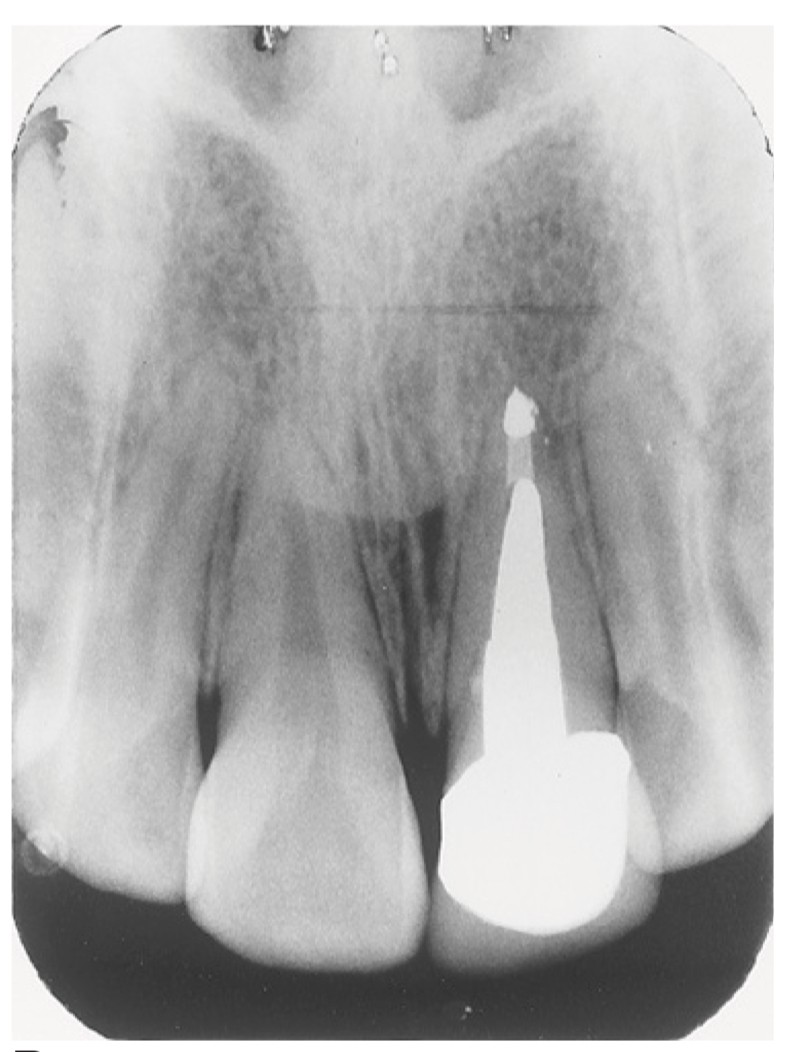

4. What option can describe the post placement in the X ray bellow for the tooth # 3.6?